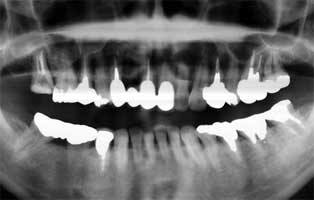

横に穴が開いていることが分かり、それも埋めて頂きました。痛みが長引いている理由

がそれかもしれないと言うことで、今度は、以前の2回と違うという期待を持てました。

一旦強引に被せて使い物になるかどうか経過うぃ見る。ダメなら穿孔した近心頬側根

をヘミセクション(歯根形態からちょっと難しそう)。それでもだめならあきらめて抜歯。

生の所に行って来ました。疲れた時に痛みがあることを話し、一応、レントゲン上もま

だ先端が炎症を起こしていて、6ヶ月ぐらいしないと回復しないと言うことで、先生か